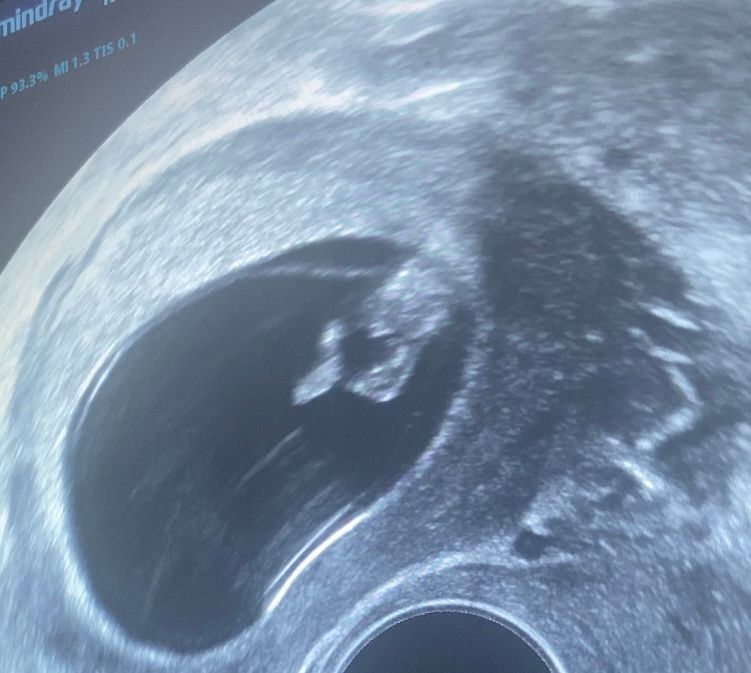

На втором снимке показывает фак?)

Serafima, это узист поймала ноги и промежность 😅там естественно пока все одинаково